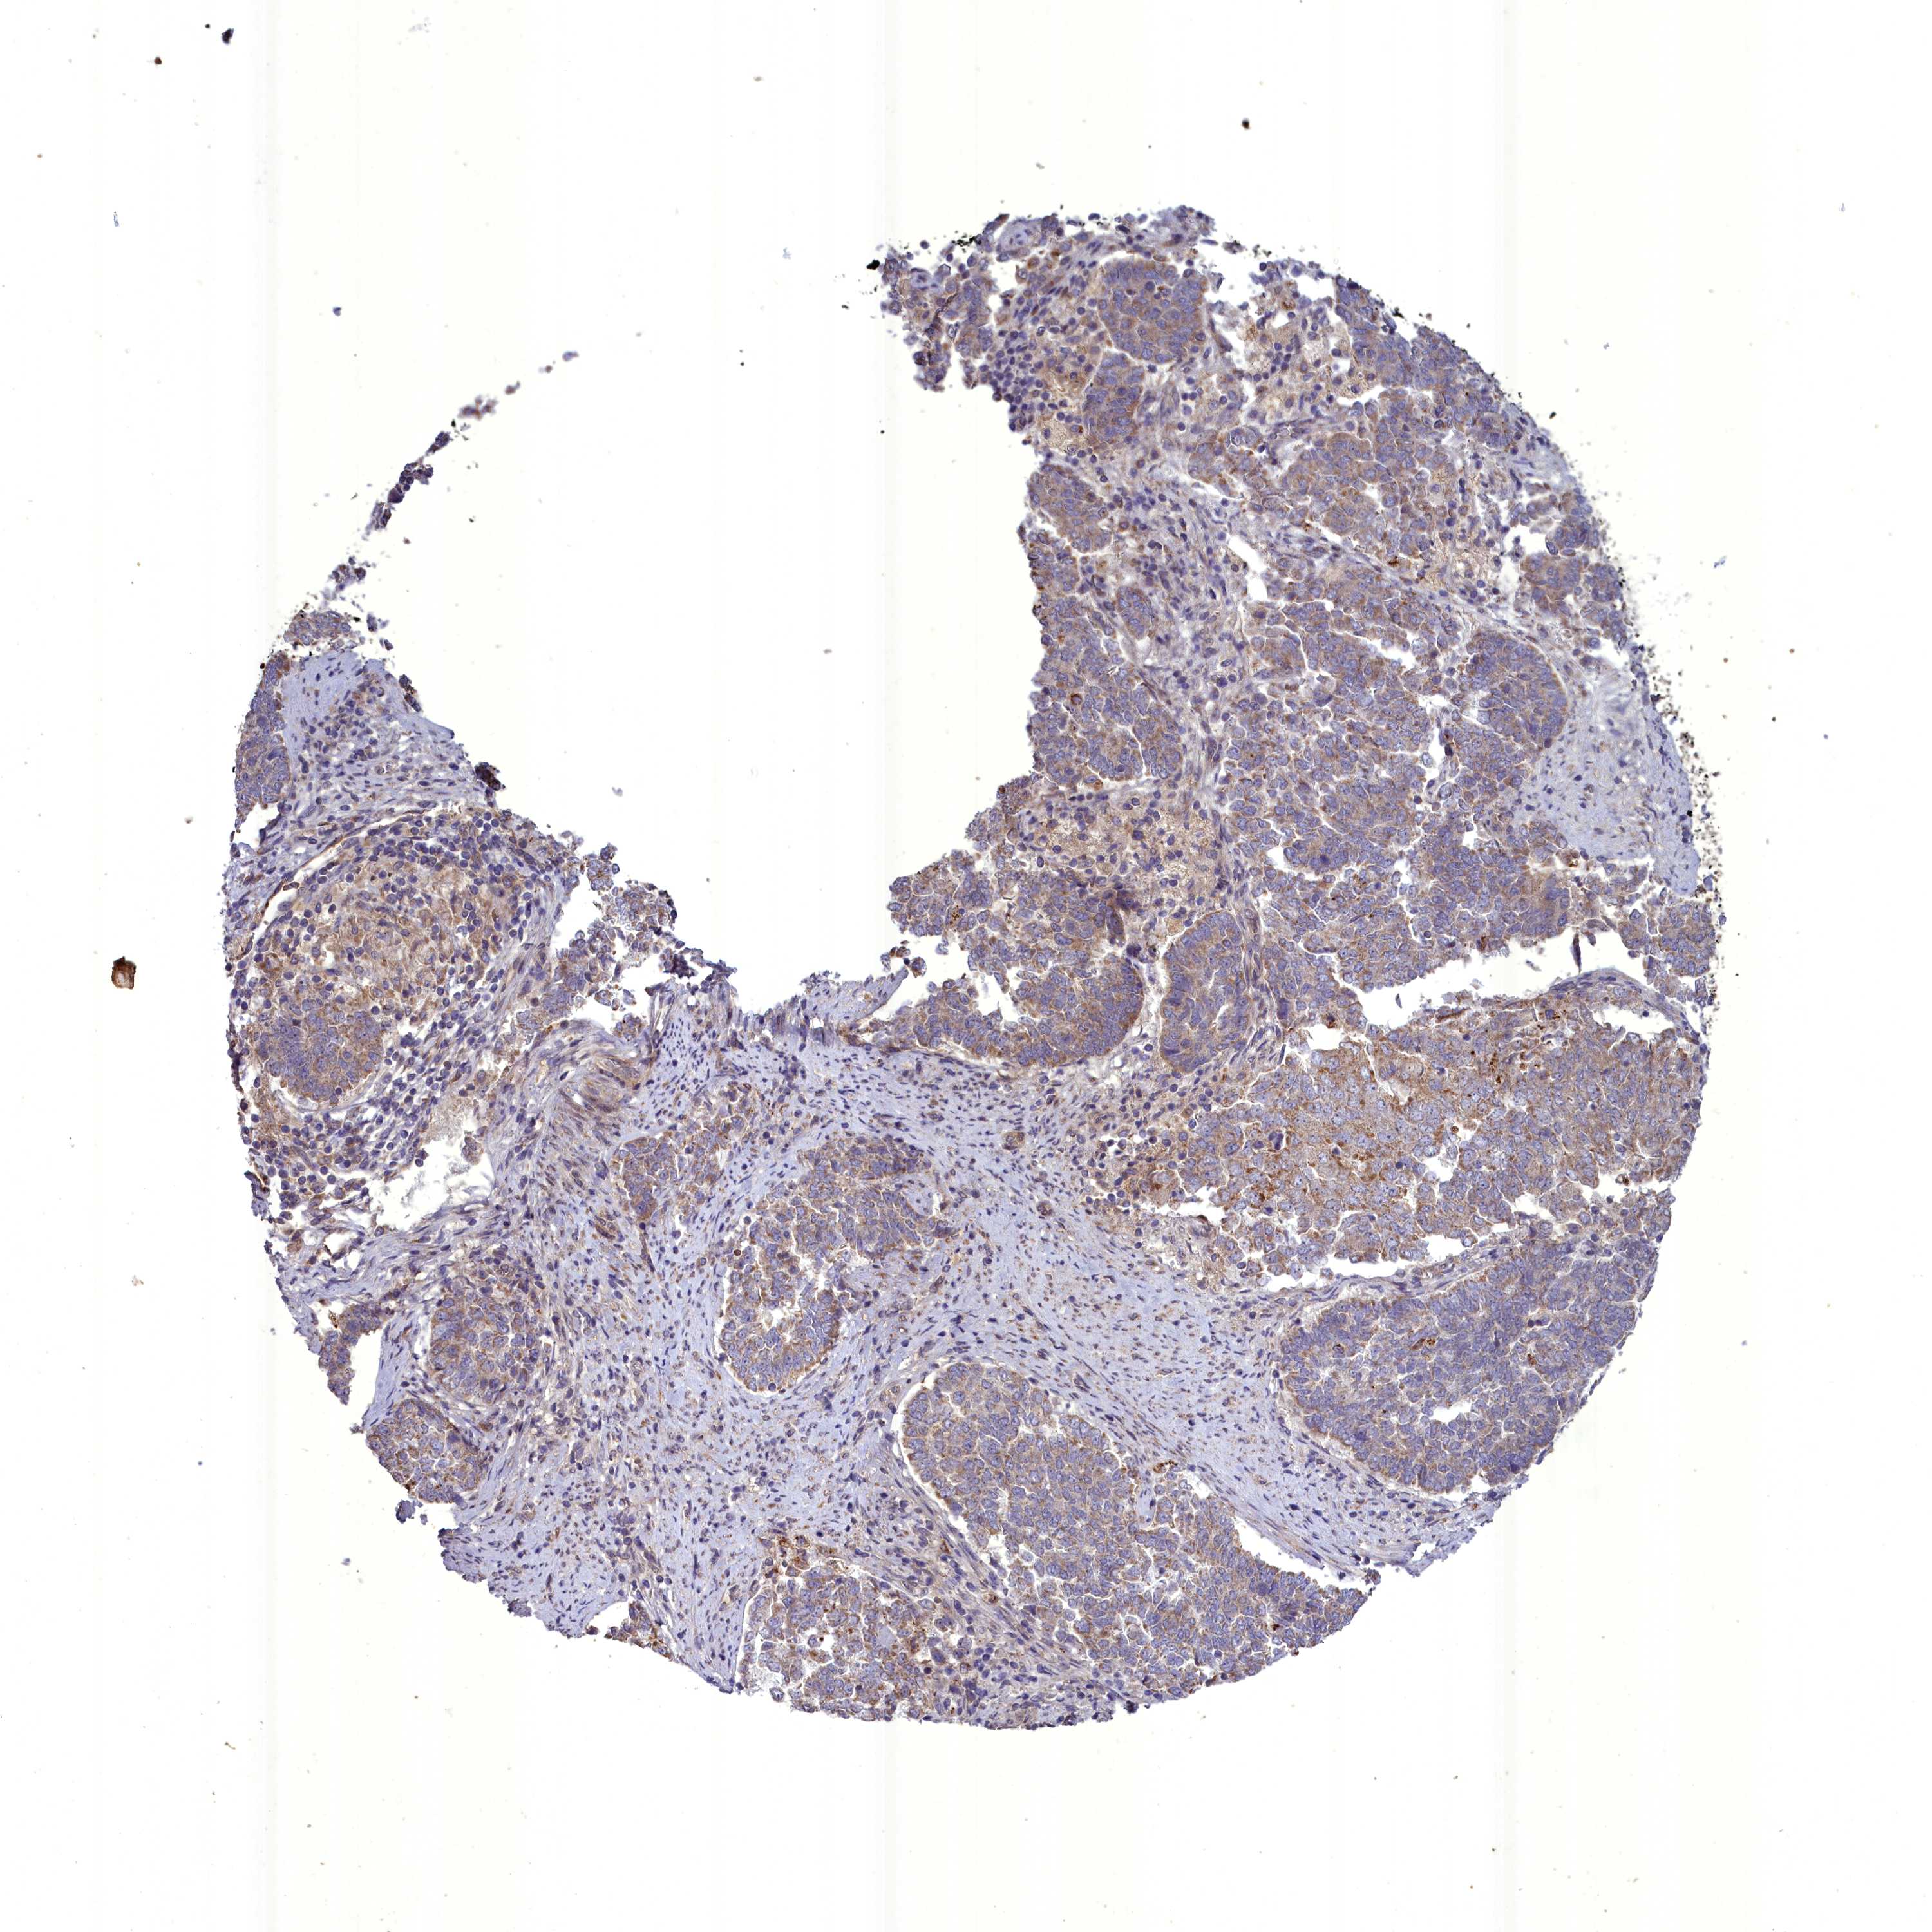

ENDOMETRIAL CANCER - Protein expressioni

A mouse-over function shows sample information and annotation data. Click on an image to view it in a full screen mode. Samples can be filtered based on level of antibody staining by selecting one or several of the following categories: high, medium, low and not detected. The assay and annotation is described here.

Note that samples used for immunohistochemistry by the Human Protein Atlas do not correspond to samples in the TCGA dataset.

Antibody stainingi

Antibody staining in the annotated cell types in the current human tissue is reported as not detected, low, medium, or high, based on conventional immunohistochemistry profiling in selected tissues. This score is based on the combination of the staining intensity and fraction of stained cells.

Each image is clickable and will lead to virtual microscopy that enables deeper exploration of all samples and also displays staining intensity scores, fraction scores and subcellular localization as well as patient and tissue information for each sample.

Antibody HPA040689

Antibody HPA043903

Staining

High

Medium

Low

Not detected

Intensity

Strong

Moderate

Weak

Negative

Quantity

>75%

75%-25%

<25%

None

Location

Nuclear

Cytoplasmic/membranous

Cytoplasmic/membranous,nuclear

Adenocarcinoma, NOS